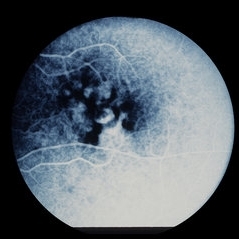

Proliferative Diabetic Retinopathy (PDR)

Sep 11 2012 by Hamid Ahmadieh, MD

Wide- field FA image of a 55-year-old woman with active PDR and the history of scatter laser photocoagulation.

Photographer: Hamid Ahmadieh, MD, Ophthalmic Research Center, Labbafinejad Medical Center, Shahid Beheshti University of Medical Sciences

Imaging device: Heidelberg HRA

Condition/keywords: preretinal hemorrhage, retinal neovascularization, scatter laser photocoagulation